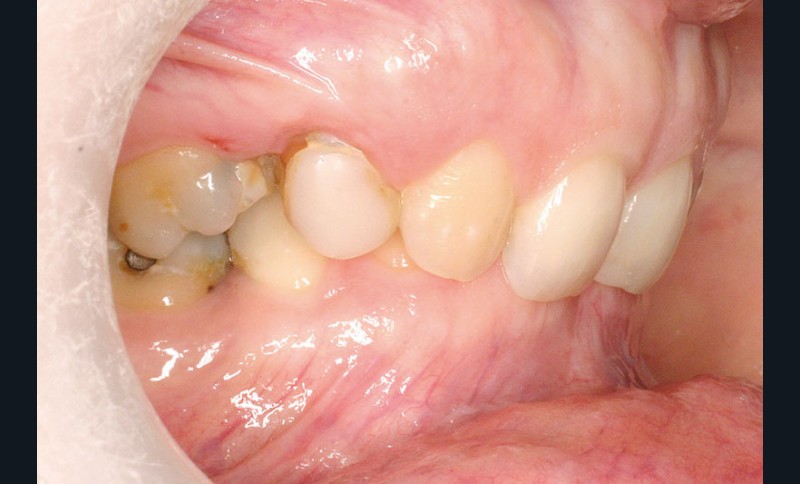

Malocclusion de classe II par rétrognathie mandibulaire dans un schéma squelettique hypodivergent (fig. 4 à 6).

On note une forte supraclusion incisive (fig. 7 à 9).

Un traitement orthodontique a déjà été effectué pendant son adolescence avec un choix de fermeture d’espaces qui a entraîné une linguoversion incisive maxillaire excessive (fig. 10), avec un préjudice esthétique important notamment sur le sourire (fig. 11 à 13).